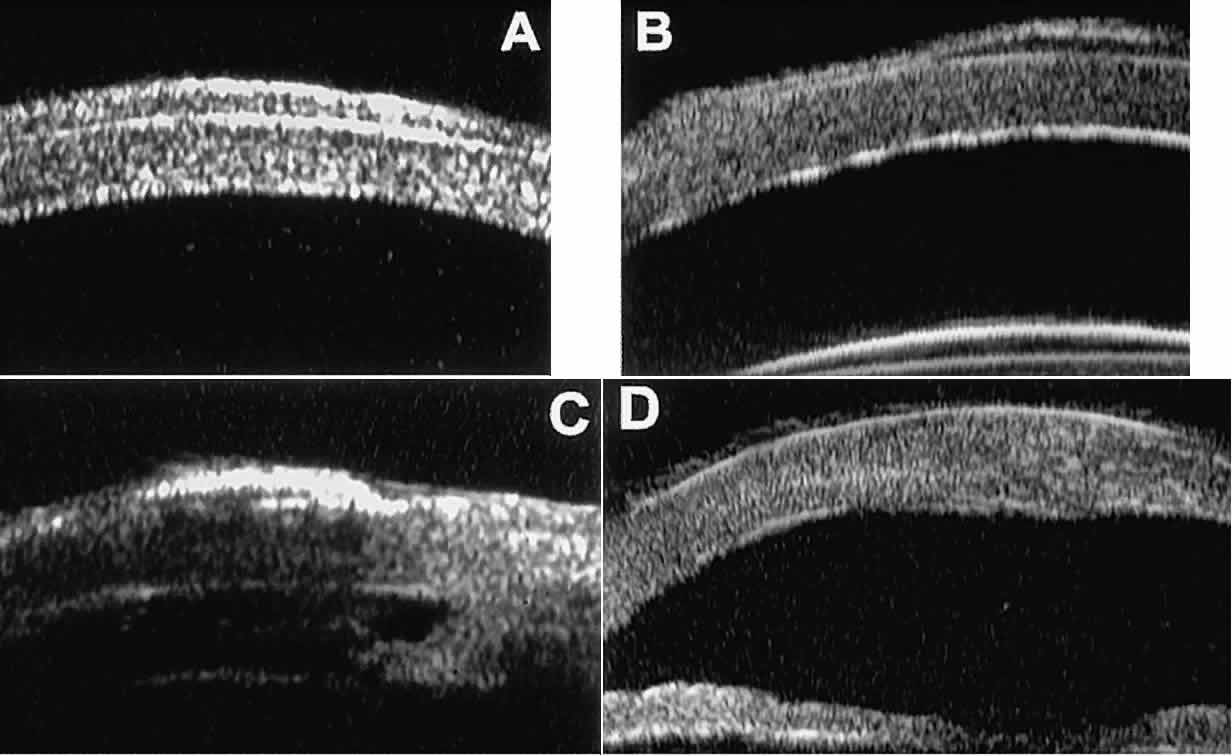

In open-angle glaucoma, UBM can be used to measure the anterior chamber angle in degrees, to assess the configuration of the peripheral iris, and to evaluate the trabecular meshwork (Fig. 9).2,4 The angle configuration can be graded and compared with gonioscopic findings. In certain patients with open-angle glaucoma, UBM can provide information that may be of some diagnostic value (Fig. 10). For example, in pigment dispersion syndrome (see Fig. 10A),6 UBM typically reveals posterior bowing of the peripheral iris (“q” configuration of peripheral iris by Spaeth classification5). In plateau iris syndrome (see Fig. 10B),7 UBM usually reveals abnormally steep anterior angulation of the peripheral iris (“s”configuration of peripheral iris by Spaeth classification5), insertion of the iris from the anterior ciliary body, and retroiridic projection of the ciliary processes. In eyes with peripheral anterior synechiae (see Fig. 10C and D), UBM can reveal the extent of iridocorneal adhesion even if the cornea is hazy or opaque.

Fig. 9. Angle configuration in eyes with open-angle glaucoma. A. Wide open angle with flat iris plane (D40r configuration by Spaeth gonioscopic grading system). B. Moderately wide angle with anteriorly bowed iris plane (C30r by Spaeth gonioscopic grading system).

Fig. 10. UBM features of special glaucoma cases. A. Pigment dispersion syndrome with posterior bowing of peripheral iris (“q” configuration by Spaeth gonioscopic grading system). B. Plateau iris syndrome with origin of iris from anterior surface of ciliary processes behind peripheral iris, slitlike narrowing of peripheral angle, and abrupt transition from steep peripheral iris to flat iris midzone. C. Broad peripheral anterior synechia with posterior bowing of nonadherent iris. D. Peripheral anterior synechia with aqueous-filled slit between site of iridocorneal adhesion and iris root after cataract extraction with implantation of posterior-chamber IOL.